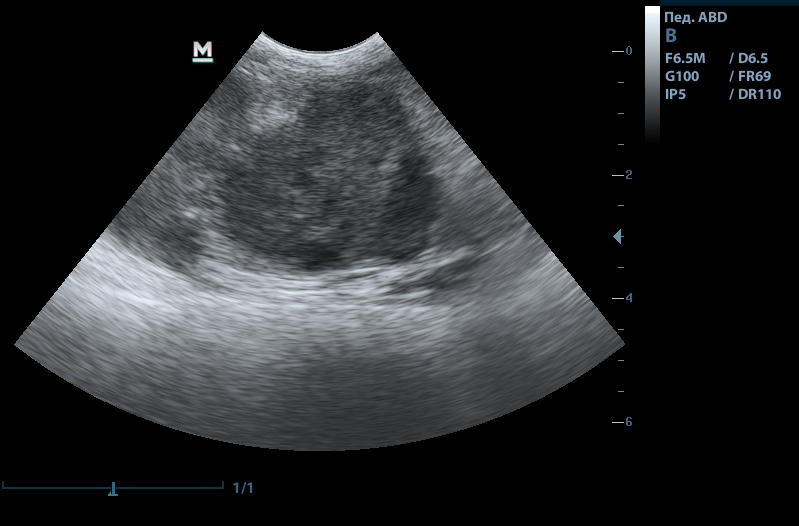

Рис.1. Новообразовательный процесс в селезенке у кота

Рис.2. Спленомегалия у кошки

Рис.3. Асцит. Визуализируется край нормальной селезенки

Рис.4. Очаговое новообразование тела селезенки

В норме на УЗИ селезенка вытянутой формы, однородная. Контур ровный, четкий, иногда видно капсулу. Визуализируются сосуды. У собак достигает в ширину 3 см, у кошек 1.5см.